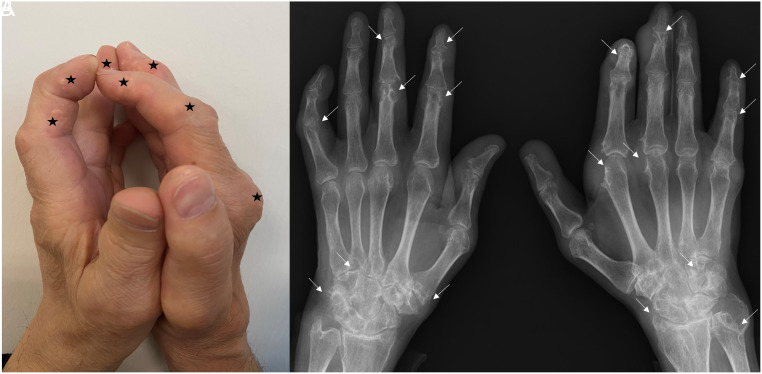

Positive Prayer Sign in Tophaceous Gout.